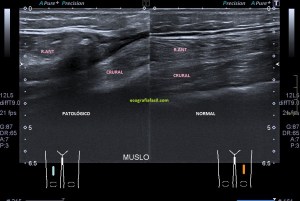

Con la eco pasa igual…cuando queremos estudiar, por ejemplo, el recto anterior del muslo en axial,perfecto…pero en longitudinal, como la imagen 2, se complica porque desde la rótula a la inserción en la cadera, tenemos mucho recorrido. En este caso hacemos lo mismo que cuando hacemos la foto del atardecer…nos ponemos en un extremo, activamos la funciona, recorremos suave y continuamente por la anatomía que queremos fotografiar y ya está…mira la pantalla y no el movimiento de tu mano,como si hicieses la foto, ves la pantalla,pero no como mueves el teléfono.